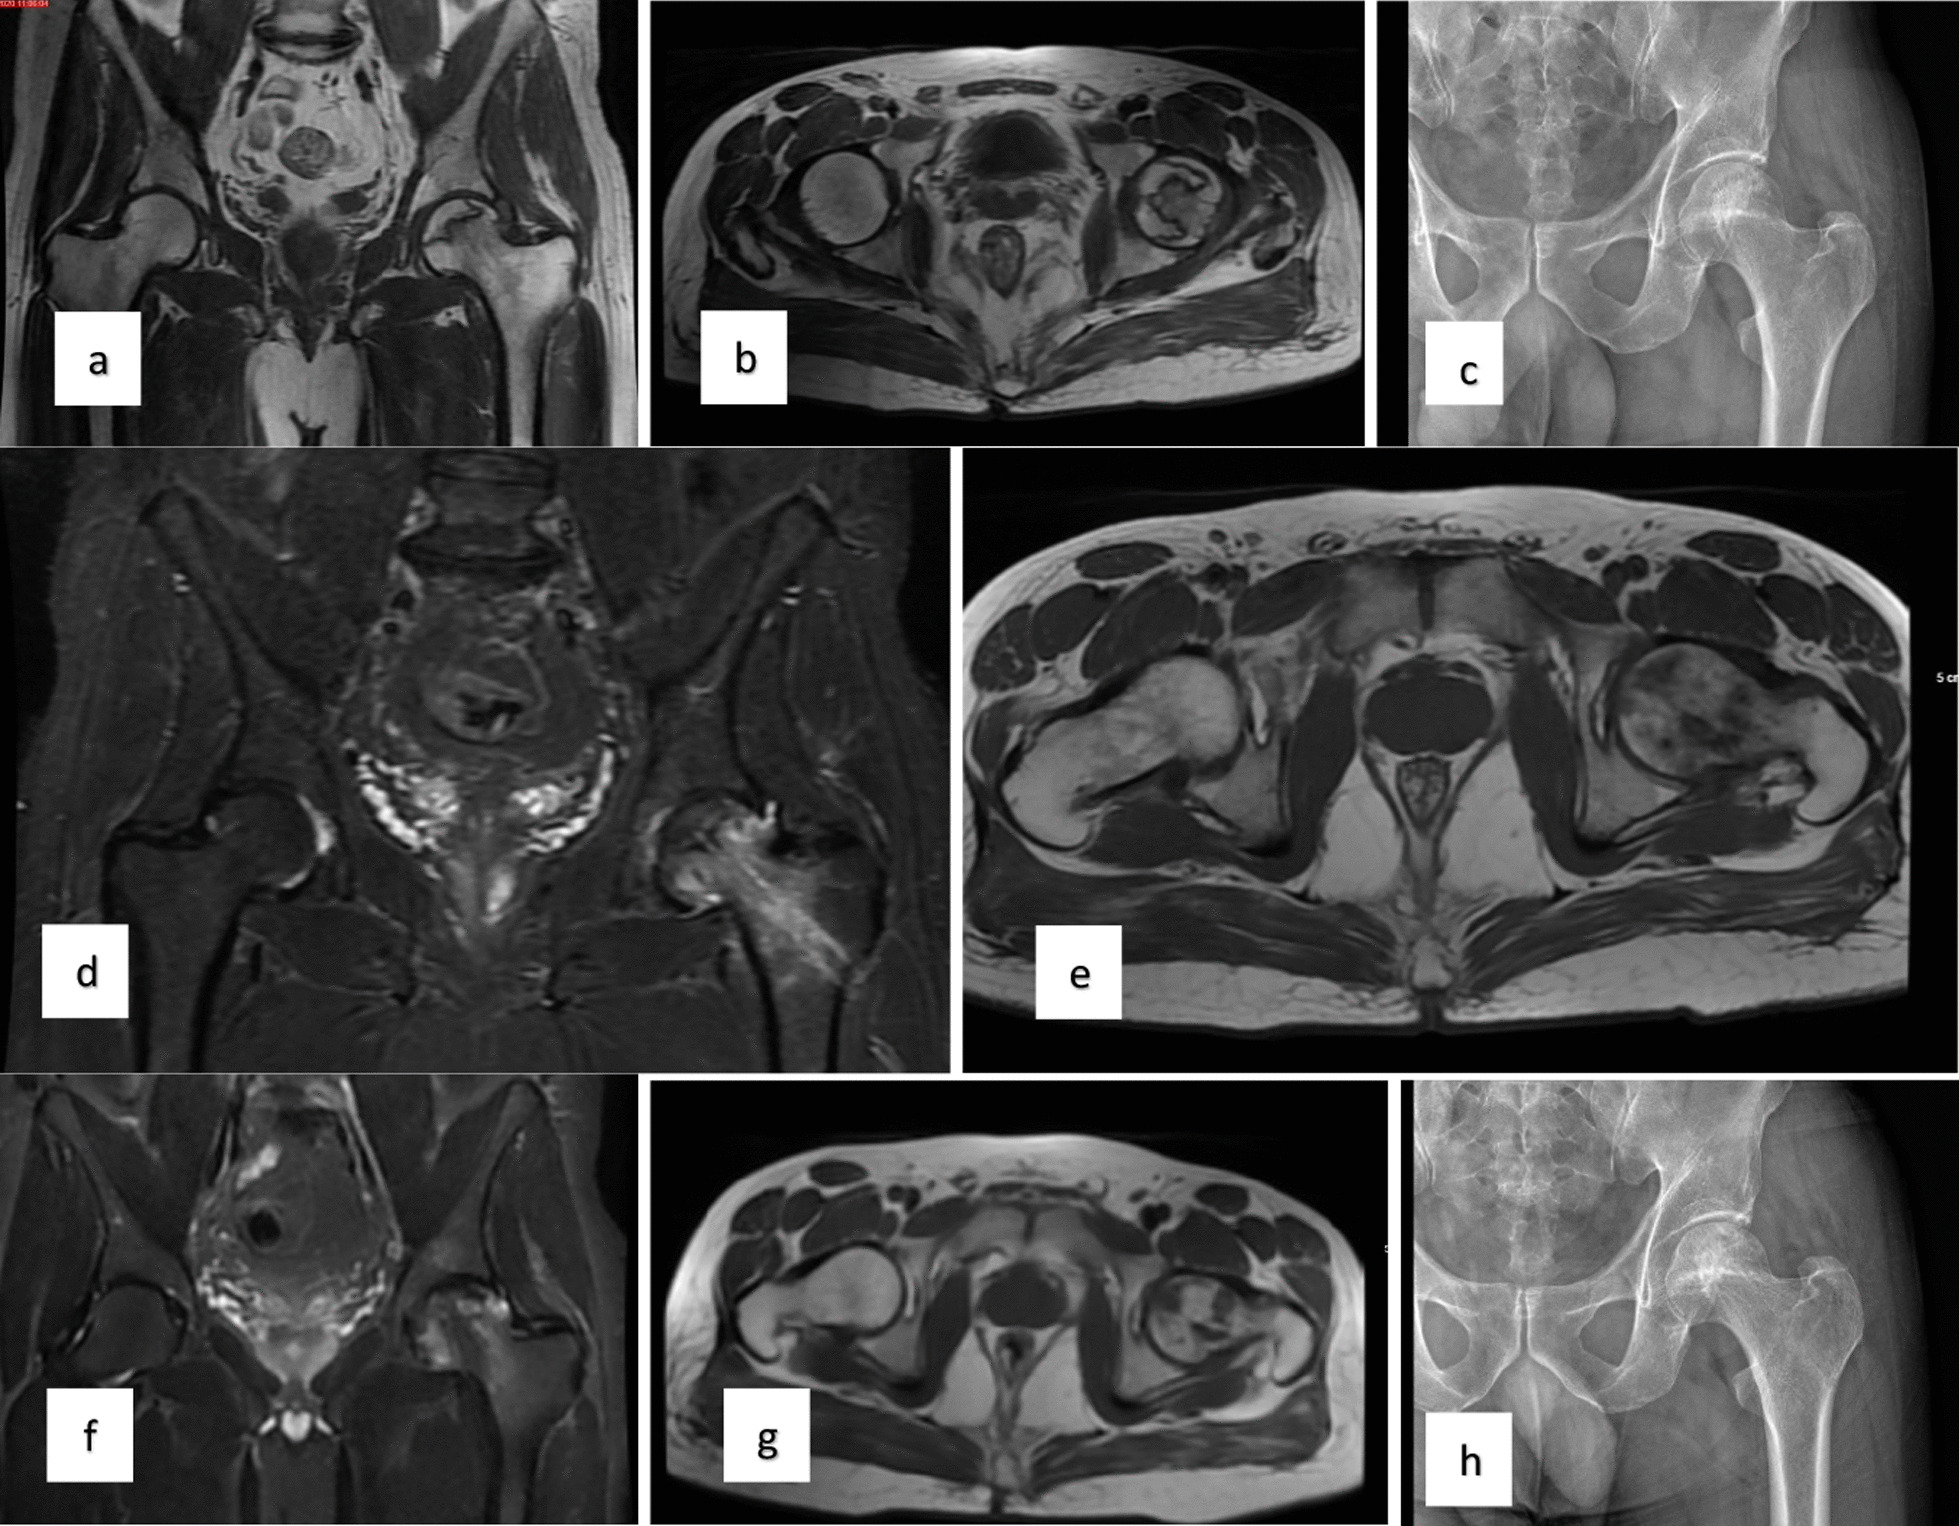

對患者的術(shù)前、3個(gè)月、6個(gè)月、1年和2年隨訪進(jìn)行評估(圖1)。

圖1:a–c左股骨頭缺血性壞死患者的術(shù)前MR和X射線圖像,d-e術(shù)后3個(gè)月的MR,f–h : 術(shù)后第二年的MR和X射線圖像